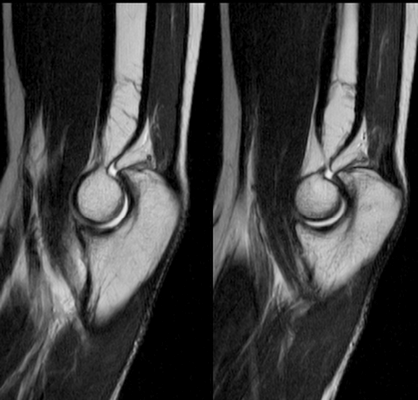

МР-снимок локтевого сочленения - вариант нормы

МРТ картина синовита, стрелками указаны участки отека костной ткани локтевого отростка

Локтевой сустав (МРТ анатомия)

Описание исследования 1 - головка лучевой кости 2 - венечный отросток локтевой кости 3 - локтевая кость 4 - локтевой отросток 5 - сухожилие трехглавой мышцы 6 - медиальная коллатеральная связка локтевого сустава 7 - лучевая коллатеральная связка локтевого сустава 8 - латеральная коллатеральная связка 9 - латеральный надмыщелок плечевой кости 10 - сухожилие двуглавой мышцы плеча 11 - плечевая мышца 12 - длинный лучевой разгибатель запястья 13 - блок плечевой кости 14 - локтевая мышца 15 - глубокий сгибатель пальцев 16 - локтевой сгибатель запястья 17 - трехглавая мышца 18 - кольцевидная связка лучевой кости 19 - двуглавая мышца плеча 20 - супинатор 21 - плечелучевая мышца 22 - круглый пронатор 23 - разгибатель пальцев 24 - лучевой сгибатель запястья 25 - поверхностный сгибатель пальцев 26 - локтевой нерв 27 - локтевой сгибатель запястья 28 - короткий лучевой разгибатель запястья 29 - общее сухожилие разгибателей 30 - общее сухожилие сгибателей и круглого пронатора 31 - бугристость лучевой кости 32 - головка плечевой кости 33 - медиальный надмыщелок плечевой кости 34 - гребень супинатора 35 - трапециевидная связка (lacertus fibrosus) 36 - наружная головка трехглавой мышцы плеча 37 - длинная головка трехглавой мышцы плеча 38 - медиальная головка трехглавой мышцы плеча 39 - общее сухожилие сгибателей